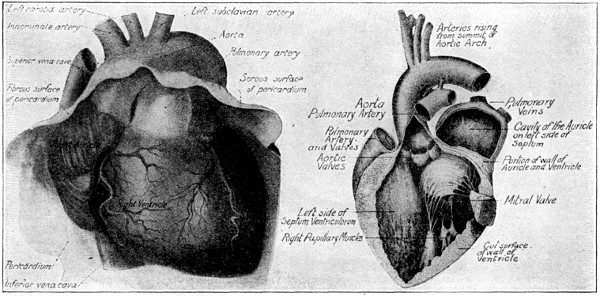

ITS STRUCTURE—ORGANIZATION INTO SYSTEMS—FUNCTIONS—SPECIAL SENSES—NERVOUS SYSTEM—PERSONAL HYGIENE—PREVENTION OF DISEASE—INTERDEPENDENCE OF BODY AND MIND—EUGENICS—ILLUSTRATIONS AND CHARTS.